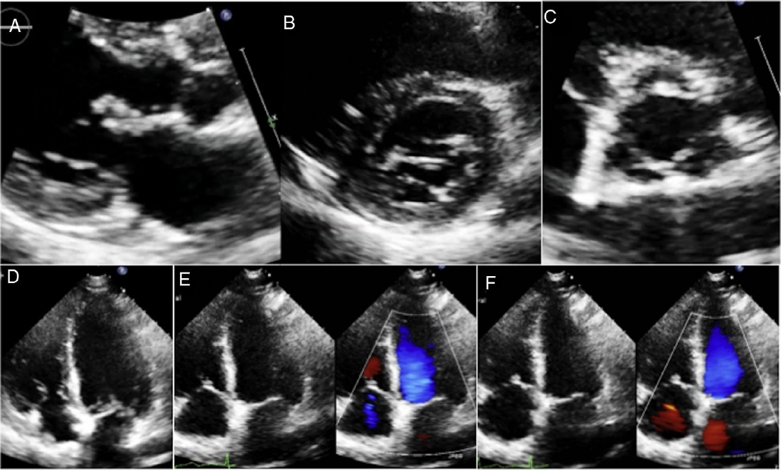

MLG is a female 58 years old with a history of rheumatoid arthritis diagnosed in December 2011 based on elevated rheumatoid factor, erythrocyte sedimentation rate and C-reactive protein, the presence of anticyclic citrullinated peptide antibody (anti-CCP), and bony erosions in the hands. She initially received treatment with immunosuppressors (methotrexate) and later with biological (abatacept) therapy with improvement and remission of the disease. She presented to the emergency room of our institution with a 3 weeks-history of a progressive dyspnea from great to moderate efforts, palpitations, fever (38.8 ◦C), malaise, dry cough and headache. On examination, she was tachycardic (HR: 101/min), with oxygen desaturation (P02 = 70%) and had bibasilar lung rales. The laboratory analysis showed leukocytosis (21.4 × 103/m3) and mild anemia (Hb – 12.7 g/dL and Htc – 40%). Blood cultures were negative. The chest computed tomography showed areas of bilateral alveolar occupation in relation to acute inflammatory process without pleural effusion. The transthoracic bidimensional (Fig. 1A–F) and three-dimensional echocardiogram revealed nodular thickening on the both mitral leaflets and in the subvalvular apparatus of the mitral valve without mitral regurgitation (Fig. 2A and B), small nodules in the aortic leaflets (Fig. 3A and prominent nodules on the tricuspid valve with mild tricuspid regurgitation (Fig. 3B), mild pulmonary hypertension, left ventricular diastolic dysfunction type I and normal left ventricular systolic function. The patient was treated with intravenous steroids and broad spectrum antibiotics with clinical improvement, but without changes in the valvular lesions. Actually she is in NYHA functional class I and the chest radiograph after the resolution of infectious process showed interstitial lung bilateral thickening and reticulonodular parahiliar and basal pattern, the left cardiac profile is abnormal and the aorta unrolled (Fig. 4).

Figure 1 Transthoracic bidimensional echocardiographic study with nodular thickening in subvalvular apparatus and mitral valve leaflet (A,B), aortic valve (C) and tricuspid valve (D,E). Mild tricuspid regurgitation was found with color flow (E,F).

Among those extra-articular features of RA are cardiovascular diseases, including pericarditis, myocardial disease, coronary vasculitis, diastolic dysfunction, accelerated atherosclerotic disease and valvular lesions.7 In the literature the prevalence of RA valvular heart disease varies from 3% to 70%.8 Valvular lesions in RA result from non specific inflammatory process in the valvular base followed by fibrosis and, sometimes, calcification. Rheumatoid granulomata are more specific findings that can be found within cusps causing valvular insufficiency.8 In a study of 184 patients with RA, the valvular lesions were monovalvar and the aortic valve was the most affected.4 In comparison to this study, our case is very rare, because it had multivalvular cardiac nodules, small in aortic valve, of moderate size in mitral leaflets with involvement of mitral apparatus and more prominent in tricuspid valve.